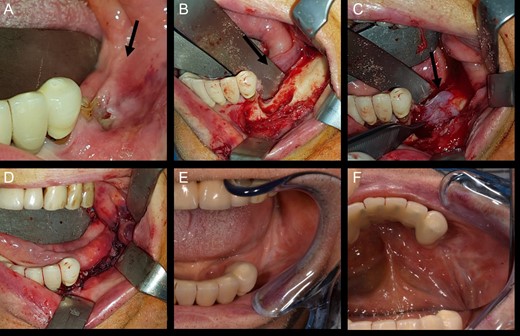

In November 2016 the patient underwent surgery under general anaesthesia (same technique used for the first patient described) (Fig. 4A–D). The mesial and distal bone curettage margins were dictated by the x-ray images (Fig. 5) which identified above all the radio-opaque areas, often associated with a periosteal reaction, as well as by the need to remove any bone sequestra present. The HAM was 3 × 3 cm2 in size and was positioned over the curetted area and under the mucosal flap.

View of mandibular alveolar process in patient 2: (A) preoperative BRONJ affected area; (B) curetted area; (C) HAM application; (D) suture of mucosal soft tissues; (E) and (F) postoperative follow-up after a period of 180 days.

The patient was submitted to a clinical and radiological follow-up 180 days after the procedure (Fig. 4E and F). The intraoral wound was completely sealed, the patient was asymptomatic and no further abscesses had developed.